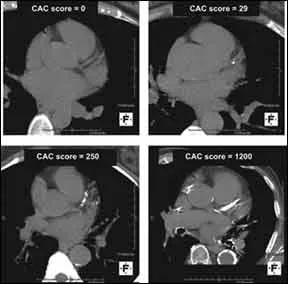

Clogged coronary arteries can not only raise your risk of heart attack, but also put you in danger of a stroke. A recent study, in fact, published in the American Heart Association journal Stroke, found that blockages in the hearts arteries can raise the odds of you having a stroke even if youre otherwise considered at low risk for the cerebrovascular event. The study, which involved more than 4,000 patients who had no previous history of strokes or heart attacks, found that those with coronary artery calcium (CAC) density levels of more than 400 were three times more likely to have a stroke than those with levels under 399.